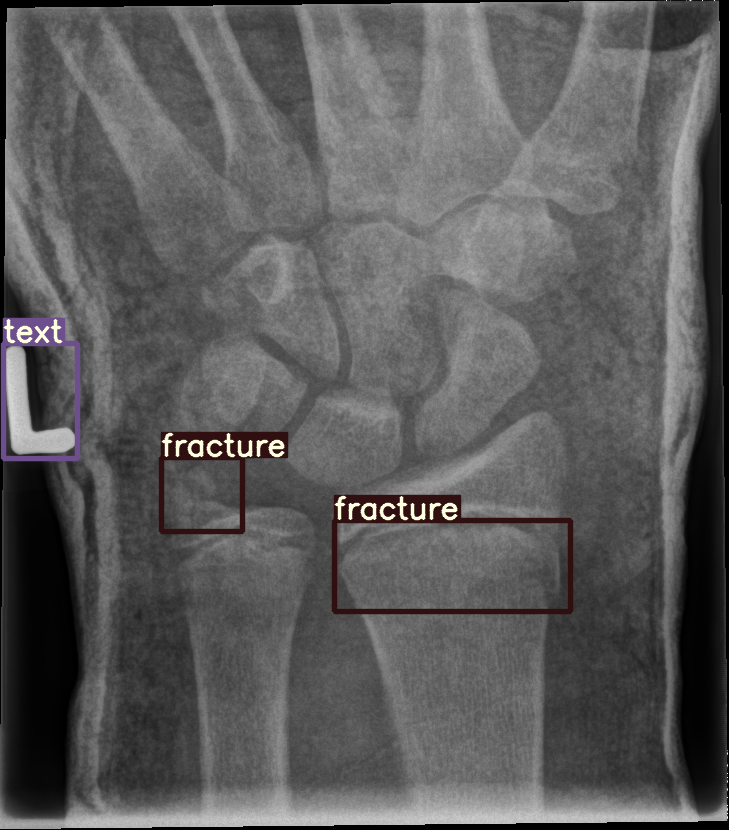

For our experiments, we selected the GRAZPEDWRI-DX images with bounding box annotations in YOLO format, which contains nine classes. Following the data division and augmentation approach outlined by [10], the dataset was randomly divided into 70%70\% training (14,23414,234 images), 20%20\% validation (4,0654,065 images), and 10%10\% testing (2,0282,028 images) sets. To further augment the training data, the number of images in the training set was doubled by adjusting the contrast and luminance of the images. The label distribution and bounding box statistics are shown in Figure 3. Examples of two training images with bounding box annotations from the GRAZPEDWRI-DX dataset are shown in Figure 4.

Refer to caption

Figure 4: Bounding box-annotated X-ray images of pediatric wrist trauma from the GRAZPEDWRI-DX dataset [8].

Figure 8: Sample of five images from the GRAZPEDWRI-DX test set, displaying ground-truth and predicted bounding box annotations: (a-e): ground-truth annotations, (f-j): YOLOv11l annotations, and (k-o): G-YOLOv11 annotations.

Table 4: Confidence scores predicted by YOLOv11l and the proposed G-YOLOv11l detectors for five images from the GRAZPEDWRI-DX test set, PR: pronator sign, FP: False positive.

8(d) fracture, fracture, text 0.770.77, 0.700.70, 0.880.88 0.760.76, 0.520.52, 0.890.89

The results in Table 4, derived from Figure 8, compares the confidence scores predicted by YOLOv11l and G-YOLOv11l detectors for five test images from the GRAZPEDWRI-DX dataset. Figure 8 contrasts ground-truth annotations with predictions from YOLOv11l and G-YOLOv11l. G-YOLOv11l shows slight improvements, such as higher confidence scores for "fracture" and "metal" in Figure 8(a) (0.700.70 and 0.890.89 vs. 0.670.67 and 0.860.86) and for "text" in Figure 8(b) (0.730.73 vs. 0.710.71). However, limitations include false positives, such as for "pronator sign" in Figure 8(c) (score 0.440.44), and lower confidence for some instances, as seen in Figures 8(d) and 8(e). While G-YOLOv11l demonstrates competitive performance, further refinements are required to improve its robustness.